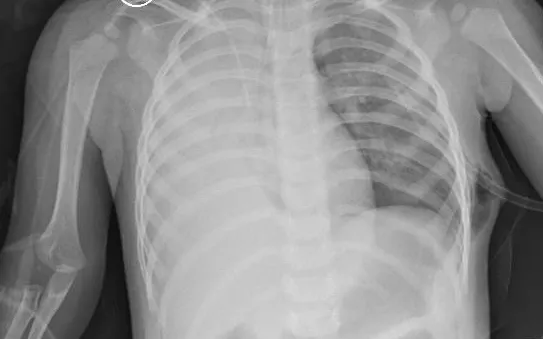

Bệnh nhân P.P.H. (16 tuổi), trước đó hoàn toàn khỏe mạnh, nhập viện trong tình trạng đau tức ngực trái dữ dội, khó thở tăng nhanh, đau lan lên vai và cánh tay trái, kèm ho khan. Khám lâm sàng cho thấy nhịp thở nhanh, mạch nhanh, phổi trái thông khí giảm rõ, gõ vang và rung thanh giảm - những dấu hiệu điển hình của tràn khí màng phổi.

Ngay sau khi xác định chẩn đoán, ekip cấp cứu đã nhanh chóng thực hiện dẫn lưu khoang màng phổi và kết nối hệ thống hút áp lực âm liên tục. Đây là thủ thuật có ý nghĩa sống còn, giúp giải phóng lượng khí tích tụ, tái lập áp lực âm sinh lý, làm phổi nở trở lại và giảm chèn ép lên tim, trung thất.